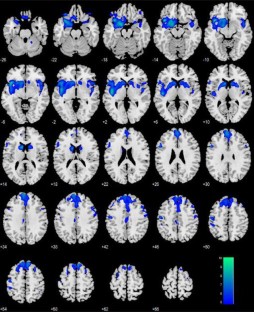

Aging is known to be associated with changes in cerebral morphometry and in regional activations during resting or cognitive challenges. Here, we investigated the effects of age on cerebral gray matter (GM) volumes and fractional amplitude of low-frequency fluctuation (fALFF) of blood oxygenation level-dependent signals in 111 healthy adults, 18–72 years of age. GM volumes were computed using voxel-based morphometry as implemented in Statistical Parametric Mapping, and fALFF maps were computed for task-residuals as described in Zhang and Li (Neuroimage 49:1911–1918, 2010) for individual participants. Across participants, a simple regression against age was performed for GM volumes and fALFF, respectively, with quantity of recent alcohol use as a covariate. At cluster level p < 0.05, corrected for family-wise error of multiple comparisons, GM volumes declined with age in prefrontal/frontal regions, bilateral insula, and left inferior parietal lobule (IPL), suggesting structural vulnerability of these areas to aging. FALFF was negatively correlated with age in the supplementary motor area (SMA), pre-SMA, anterior cingulate cortex, bilateral dorsal lateral prefrontal cortex (DLPFC), right IPL, and posterior cingulate cortex, indicating that spontaneous neural activities in these areas during cognitive performance decrease with age. Notably, these age-related changes overlapped in the prefrontal/frontal regions including the pre-SMA, SMA, and DLPFC. Furthermore, GM volumes and fALFF of the pre-SMA/SMA were negatively correlated with the stop signal reaction time, in accord with our earlier work. Together, these results describe anatomical and functional changes in prefrontal/frontal regions and how these changes are associated with declining inhibitory control during aging.

Fig. 1